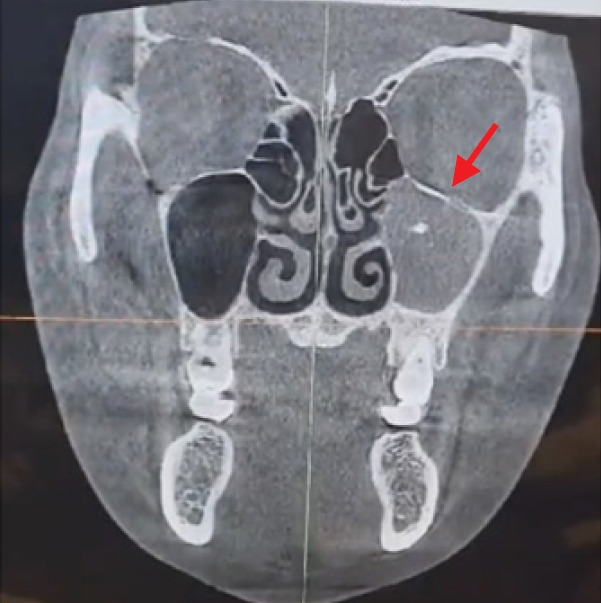

本病例报告描述了我们对一名 35 岁女性顽固性肛周脓肿的治疗。脓肿是在颧骨缩小手术后形成的,在手术过程中,术前存在的真菌球没有得到处理。我们的综合治疗方法包括功能性内窥镜鼻窦手术、真菌球摘除、脓肿引流和清创。术后两周,患者症状缓解。术后 6 个月的随访没有发现复发或并发症的迹象,患者对功能和美观效果均表示满意。该病例强调了彻底术前评估的重要性,并提高了人们对无症状病变未经治疗的潜在风险的认识,因为这些病变可能会发展并导致进一步的并发症。

This case report describes our treatment of a persistent periantral abscess in a 35-year-old woman. The abscess developed following a zygoma-reduction surgery, during which a preexisting fungal ball had not been addressed. Our comprehensive treatment approach included functional endoscopic sinus surgery, fungal ball removal, abscess drainage, and debridement. Two weeks postoperatively, the patient's symptoms had resolved. A 6-month postoperative follow-up revealed no signs of recurrence or complications, and the patient reported satisfactory functional and aesthetic results. This case underscores the importance of thorough preoperative evaluations and raises awareness about the potential risks of untreated asymptomatic pathologies, which can potentially progress and lead to further complications.